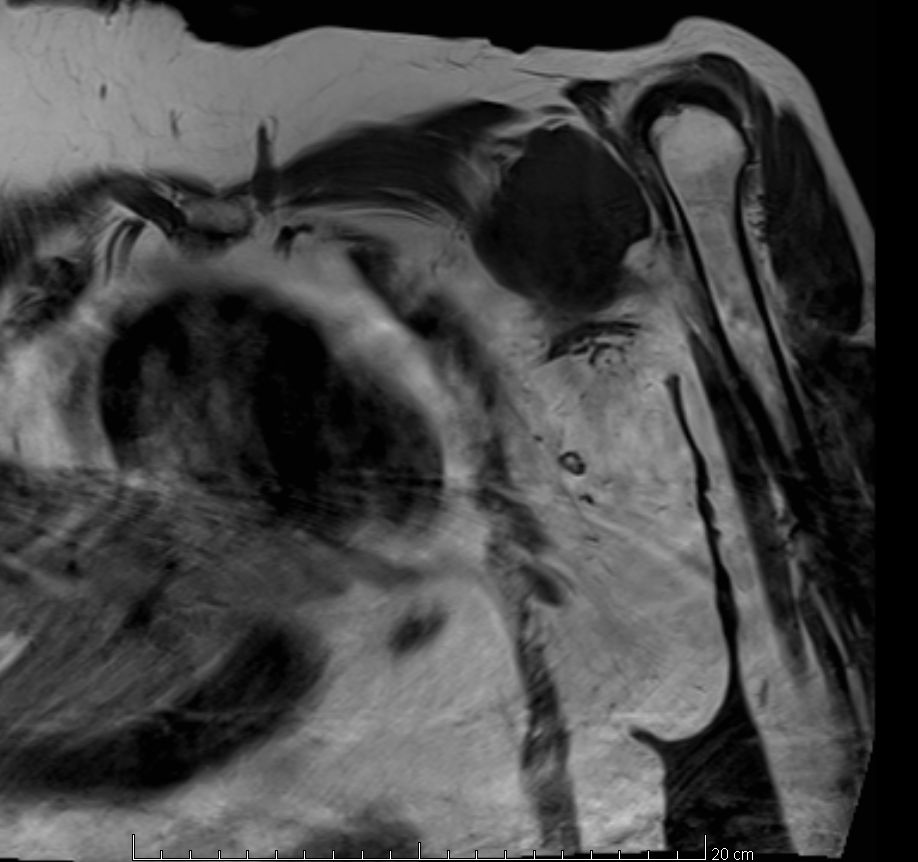

| Diagnostik | 56-jährige Frau mit einer derben, wenig verschieblichen Tumorbildung untergalb der linken Clavikula. ![]() |